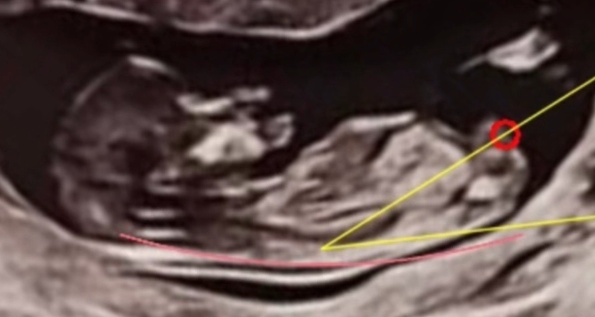

Understanding Nub Theory

Nub theory is based on the angle of the genital tubercle (or "nub") visible in ultrasound scans around 12 weeks. Research suggests that the angle of the nub can indicate the baby's gender.

- Angle pointing upward (≥30°): Likely a boy

- Angle parallel or downward (<30°): Likely a girl